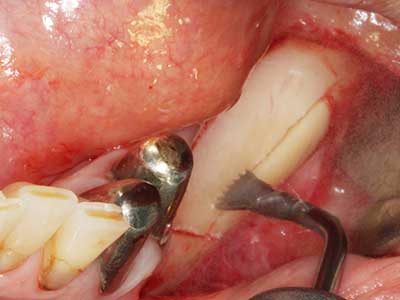

Indicazione: preparazione vicino ai nervi

Come descritto in precedenza, le indicazioni per la piezochirurgia si possono trovare anche nel campo della chirurgia odontoiatrica conservativa. Delle puntine particolari semplificano l'esposizione delle punte delle radici e facilitano la protezione dei nervi e delle membrane mucose del seno, in particolare nella regione dentale superiore e posteriore e in quella premolare inferiore. Le puntine angolate diamantate si utilizzano per preparare con precisione la cavità della resezione che ospiterà il materiale di riempimento della radice retrograda per l'otturazione apicale sigillata. Grazie alla tecnologia a ultrasuoni le puntine possono essere estremamente sottili, quindi la visibilità e le dimensioni di accesso della cavità sono migliori. Di conseguenza, l'applicazione della chirurgia a ultrasuoni per questa indicazione è una delle procedure standard per la resezione apicale (Del Fabbro, Tsesis et al. 2010, Scarano, Artese et al. 2012).

Indicazione: resezione apicale

Quando le procedure chirurgiche vengono eseguite sull'osso nelle immediate vicinanze di strutture sensibili, come vasi sanguigni o nervi, gli strumenti rotanti pongono un rischio significativo di lesione iatrogena. I dispositivi piezoelettrici possono essere utili per la preparazione delle coperture ossee e la rimozione del tessuto duro in prossimità dei nervi, in particolare per la loro esposizione dopo una lesione iatrogena, ma anche durante la lateralizzazione dei nervi per le procedure di resezione e ricostruzione o il posizionamento di impianti (figg. 17-20). Il contatto leggero tra puntina piezoelettrica e nervo non causa generalmente danni, ma se si procede senza prestare attenzione con movimenti a sega o raccordi con residui di substrati ossei possono verificarsi danni al nervo temporanei o anche permanenti. Il rischio di danno, tuttavia, è considerato sostanzialmente inferiore al rischio presente utilizzando seghe o frese (Pereira, Gealh et al. 2014).